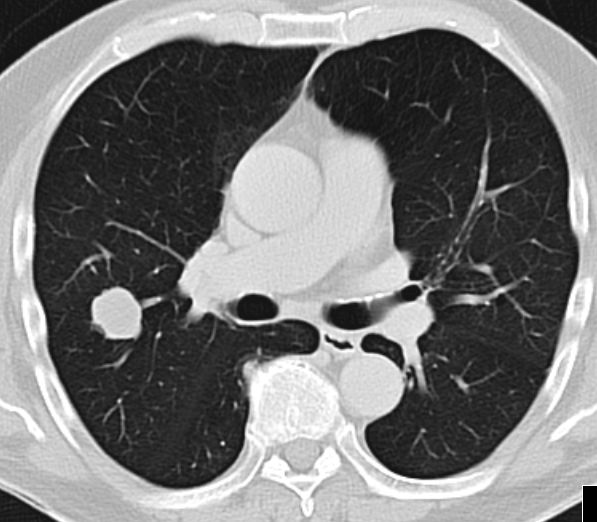

| Beispiele bildgebender Diagnostik von Fernmetastasen | Knochenmetastasen![]() |

Lungenmetastasen![]() |